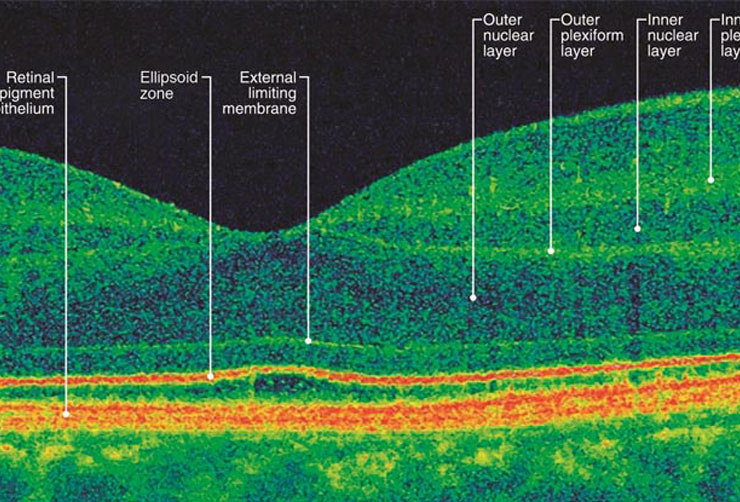

OCT

Optical coherence tomography (OCT) is a non-invasive imaging test. OCT uses light waves to take cross-section pictures of your retina.

With OCT, your ophthalmologist can see each of the retina’s distinctive layers. This allows your ophthalmologist to map and measure their thickness. These measurements help with diagnosis. They also provide treatment guidance for glaucoma and diseases of the retina. These retinal diseases include age-related macular degeneration (AMD) and diabetic eye disease.